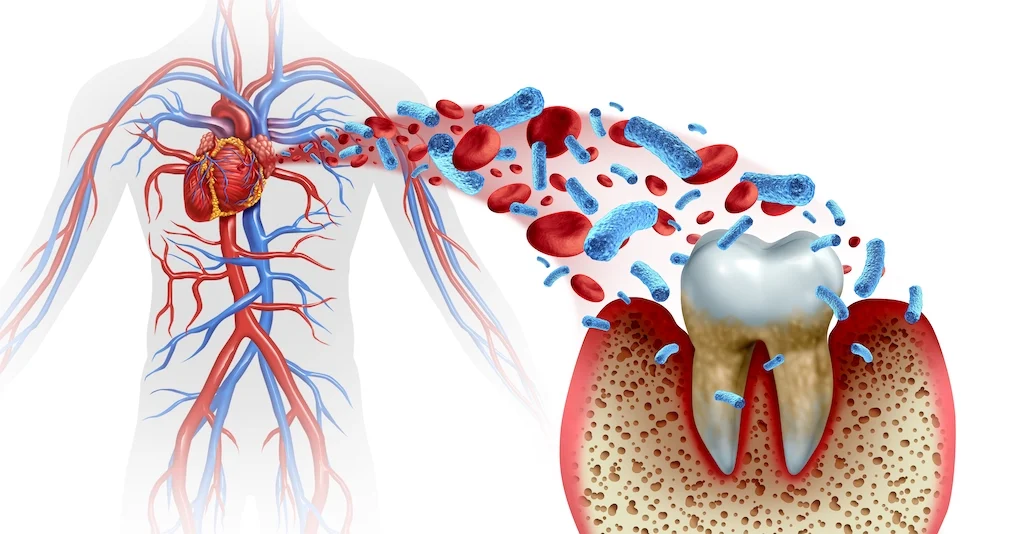

The Link Between Heart Disease and Oral Health – What Katy Residents Should Know

It’s necessary for you to understand the connection between your oral health and heart disease, as studies have shown that poor dental hygiene can increase your risk of cardiovascular issues. The health of your mouth can reflect and impact your overall well-being, making it vital to prioritize dental care. In this post, we’ll explore how […]

The Connection Between Oral Health and Chronic Diseases

Oral health is more than just about having a bright smile; it’s a critical component of overall health and well-being. Emerging research continues to highlight the significant connections between oral health and various chronic diseases. This intricate relationship underscores the importance of maintaining good oral hygiene not just for dental health, but as a crucial […]

6 Types of Dental Health Services for You and Your Family

Did you know that there are various scientific studies that show a correlation between inflammation that is associated with gum disease and illnesses such as diabetes and heart disease? Almost everybody understands that it is important to go to the dentist on a regular basis. But it is less common for people to know why […]